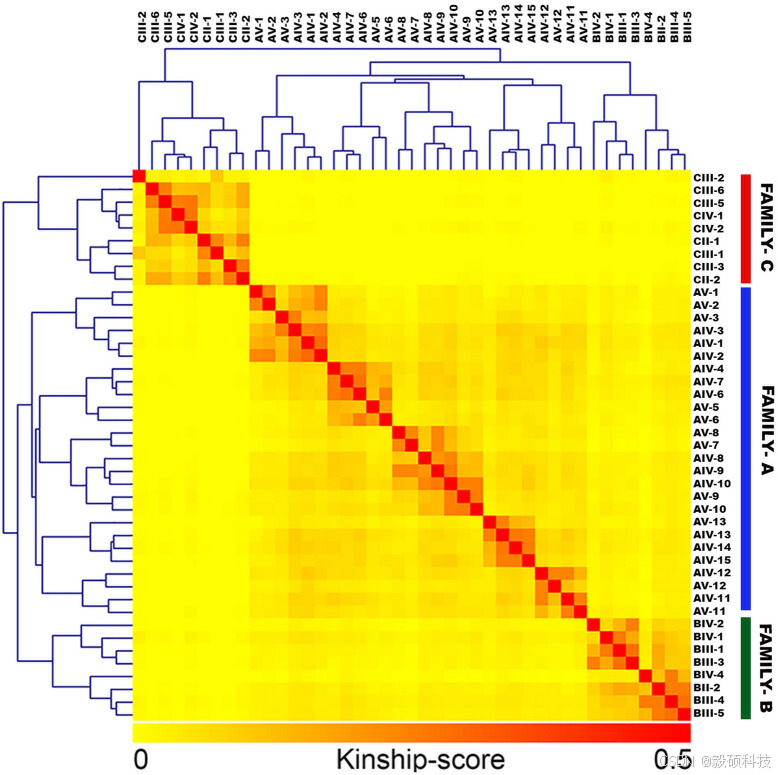

研究组使用 Amrita HCM 的 22 例 PRKAG2 心肌病患者的形态学表现和临床病程,这些患者分属三个无血缘关系的家族。家庭 A(FGD0128)、家庭 B(FGD0137)和家庭 C(FGD0314 )。

研究组只筛选了罕见变异(MAF < 0.1%),然后确定了预测会对蛋白质功能产生影响和/或与疾病相关的罕见变异。在疾病遗传模式进行叠加后,筛选出了通过受影响和未受影响的家庭成员进行遗传的致病变异。发现了一个致病性常染色体p.Arg302Gln突变,该突变影响了 AMP/ ATP 结合口袋。通过对所有个体进行 Sanger 测序,验证了PRKAG2 突变。该突变在所有三个家族中都显示出完全的表型基因型相关性。因此研究组进行了无偏的亲缘关系分析,以检查所有家系是否来自同一创始群体。在对亲缘关系矩阵的分层聚类分析中,这三个家系之间没有任何亲缘关系,并形成了三个不同的聚类。

图7 对 3 个家系的亲缘关系分析表明,这些家系完全没有亲缘关系,也没有始祖效应